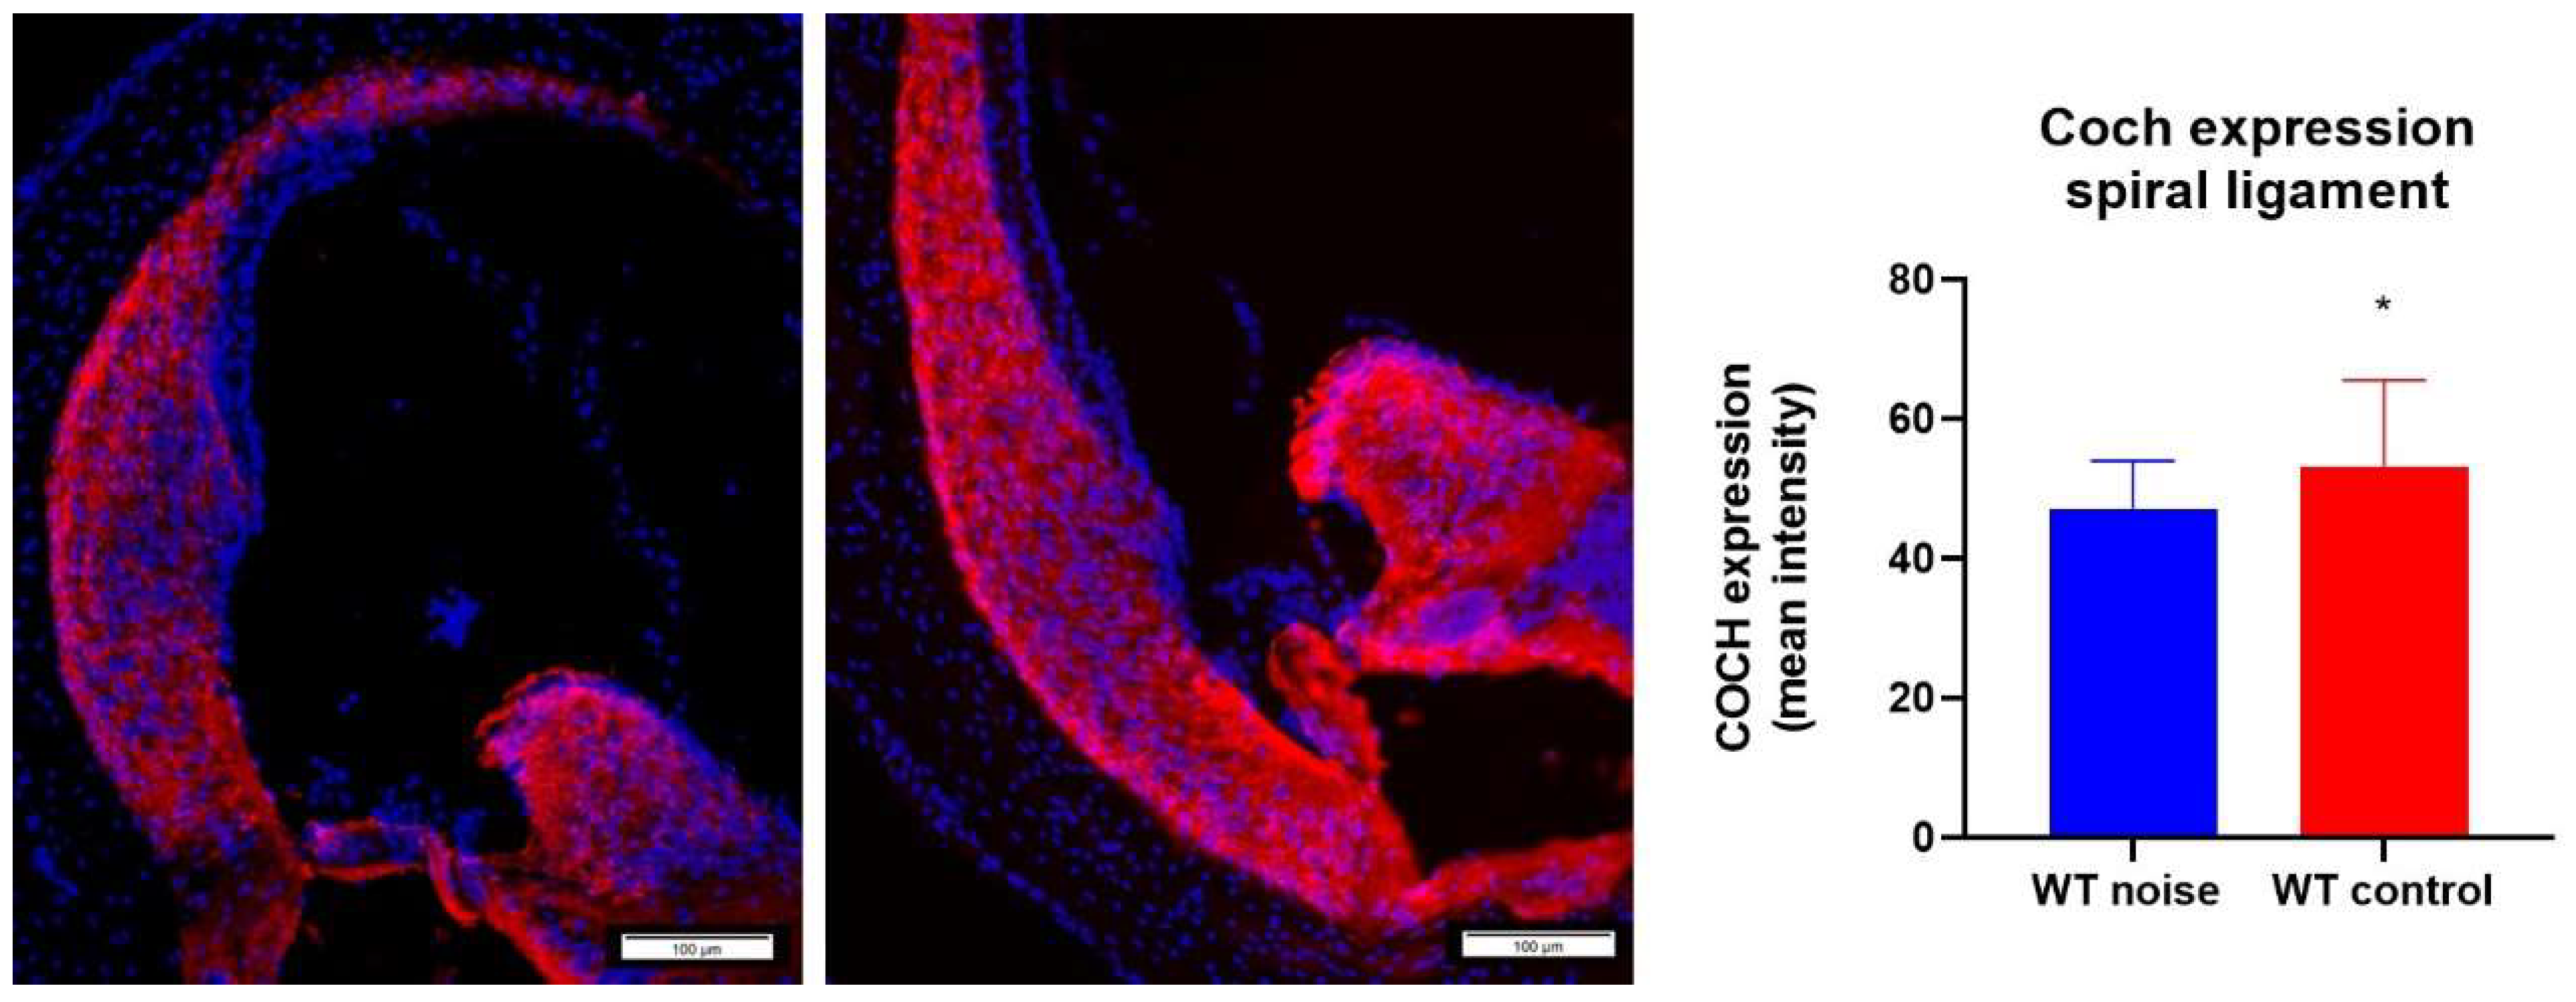

2.7. Noise Trauma Reduces Cochlin Immunoreactivity in the Spiral Ligament

An anti-Coch antibody was used to stain for the COCH protein in the spiral ligament. It was observed that Coch+/+ mice that were exposed to noise had a significant lower expression level of the COCH protein than Coch+/+ mice that were not exposed to noise (Figure 9).

Figure 9.

Cochlin expression (COCH antibody, red) in the spiral ligament between Coch+/+ mice that were exposed to noise (n = 13) (left) and Coch+/+ mice that belong to the control group (n = 9) (middle). Coch expression was measured in ImageJ. A significant difference was found in Coch expression between both group where the noise exposure group had significant lower levels of Coch expression than the wildtype control group. * indicates p < 0.05.

To assess whether cochlin could be responsible for the difference in hearing thresholds that was observed between Coch+/+ and Coch−/− mice after noise exposure, Coch expression in wildtype mice was assessed using an anti-COCH antibody. We found that Coch expression was significantly decreased in Coch+/+ mice after noise exposure, which could be explained by the observation of Seist et al. that cleaved cochlin is upregulated in Coch+/+ mice following noise exposure [18].